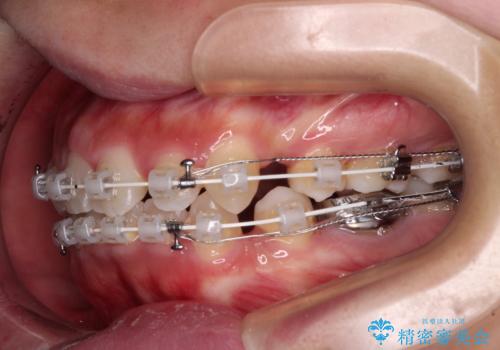

- 矯正装置

- 審美装置

- 前歯のデコボコやクロスバイト、口元の突出感を気にして来院された患者様です。

上下左右の第一小臼歯4本を抜歯して、ワイヤー装置にて矯正治療を行うこととしました。